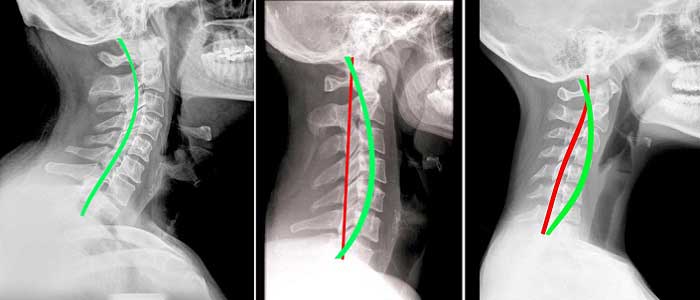

- Boyun düzleşmesi,boyunun doğal ‘’C’’ şeklinin bozulması şiddetli ağrılara neden olabilir.

Boyun bölgesinde 7 adet omur vardır bu omurlar yandan tepe noktası boynun ön bölgesi olan ’C ‘ harfini andırır. Boyun bölgesindeki omurga eğriliğini servikal lordoz olarak ifade ediyoruz. Bu eğri tamamen normaldir başın yükünü taşımak için olması gereken bir eğriliktir, çünkü kafa ve omurganın stabilize edilmesine yardımcı olur. Fakat eğrinin düzleşmesi yani fizyolojik lordoz olarak ifade ettiğimiz açının azalması veya kaybolup ’ I ‘ şeklini alması durumunda boyun düzleşmesi olarak ifade ettiğimiz klinik tablo ile karşılaşırız.Bazen bu eğri daha da ilerleyip tersine açılanma yapmaya başladığında daha da ciddi bir sorunla karşı karşıyayız demektir.

İyileşmeyeceği düşünülen boyun düzleşmesi, travmalardan sonra gelişen kas ve bağ zedelenmeleri gibi sorunlar, aslında manuel terapi sayesinde çok kolay bir şekilde iyileştirilebilmektedir. Bu tür rahatsızlığı olan kişiler, genellikle bu sorunlarının iyileşmeyeceğini düşünürler ve yaşamları boyunca bu sorunla yaşamak durumunda kalırlar. Düzleşme, tedavi edilmediğinde kireçlenme ve fıtığı da tetikleyebilmektedir.